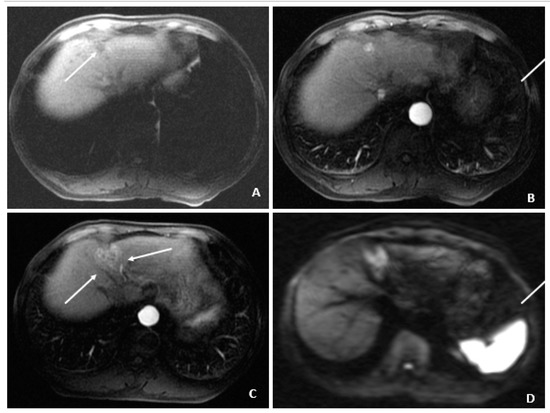

Figure 7.

Recurrent HCC after cryoablation (August 2009 and July 2010). (A) At 3 months following cryoablation, the axial T1-weighted fat-suppressed precontrast image shows a small hypointense lesion (arrow) above and in proximity to the recently ablated HCC. (B) The corresponding arterial-phase postcontrast image shows hyperenhancement (arrow), but additional features (i.e., washout, capsule appearance, etc.) were not observed. (C) Months later, a follow-up MRI showed threshold growth of the hyperenhancing lesion (arrows). (D) The corresponding diffusion-weighted image shows diffusion restriction (arrows) and helps to confirm the diagnosis of HCC (as an ancillary feature); washout was also evident (not shown), confirming the diagnosis of HCC.